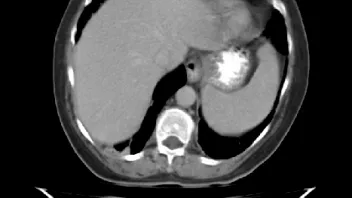

ist jemand unter Euch der sich auskennt mit CT Aufnahmen ?

Ich habe 3 Stück angehangen, sie stammen aus einem CT der Abdomen.

Möglich das es eine Serie eines Querschnitts darstellt Bild 1 zeigt den Start,Bild 2 eines aus den mittleren Aufnahmnen und Bild 3 das letzte dieser CT Serie.

Da ganz gezielt auf ein und die gleiche Stelle gehalten wurde mit sagenhaften über 80 Einzelaufnahmen interessiert mich brennend um die Darstellung welches Organges es sich bei diesen Aufnahmen handelt und ob darauf etwas bedenkliches eingekreist wurde.

Herzlichen dank für die Hilfe,falls jemand es einordnen kann. Mir ist die Antwort darauf so wichtig weil es sich um Aufnahmen meiner Mutter handelt die nicht mehr unter uns ist.